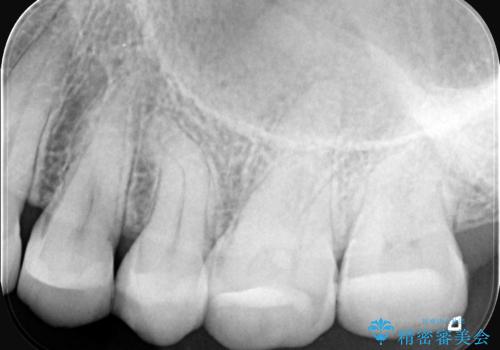

- 右上の歯の痛みを主訴にご来院されました。精密な診査の結果、虫歯が深く進行し、歯の神経(歯髄)にまで炎症が及んでいると診断。このままでは痛みが治まらず、歯を失うリスクもあるため、まず痛みの原因である感染した神経を取り除く根管治療を提案しました。根管治療によって歯の土台を整えた後、歯の破折を防ぎ長期的に機能させるため、**クラウン(被せ物)**を装着して修復する治療計画を立案しました。